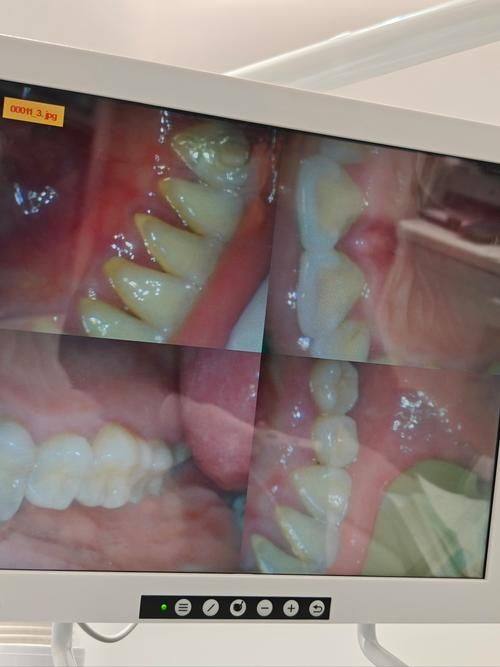

每个人的口腔环境和生活习惯不同,牙石形成的速度也会有较大差异。对于牙石形成较快的患者,可能三个月就需要洁治一次。这类患者可能本身唾液成分特殊,容易促进牙石的形成;或者平时喜欢吃一些黏性较大、富含糖分的食物,这些食物更容易附着在牙齿表面,加速牙石的堆积。

另外,一些患有特殊疾病的患者,洗牙频率也需要根据具体情况进行调整。例如,患有糖尿病的患者,由于血糖控制不佳时,口腔内的细菌更容易滋生,导致牙石形成加快,所以可能需要缩短洗牙的间隔时间。而正在接受正畸治疗的患者,牙齿上佩戴的矫治器会增加清洁的难度,牙菌斑和牙石更容易堆积,也可能需要增加洗牙的频率。

其次,可以询问专精的口腔医生。医生会根据你的口腔检查结果,包括牙齿的清洁程度、牙龈的健康状况、牙石的分布和量等,为你制定个性化的洗牙计划。此外,医生还能根据你的生活习惯、饮食习惯等因素,综合判断你牙石形成的速度,从而给出更正确的洗牙建议。